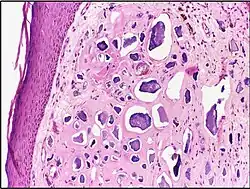

-

Calcinosis cutis -

Calcinosis cutis in human tissue